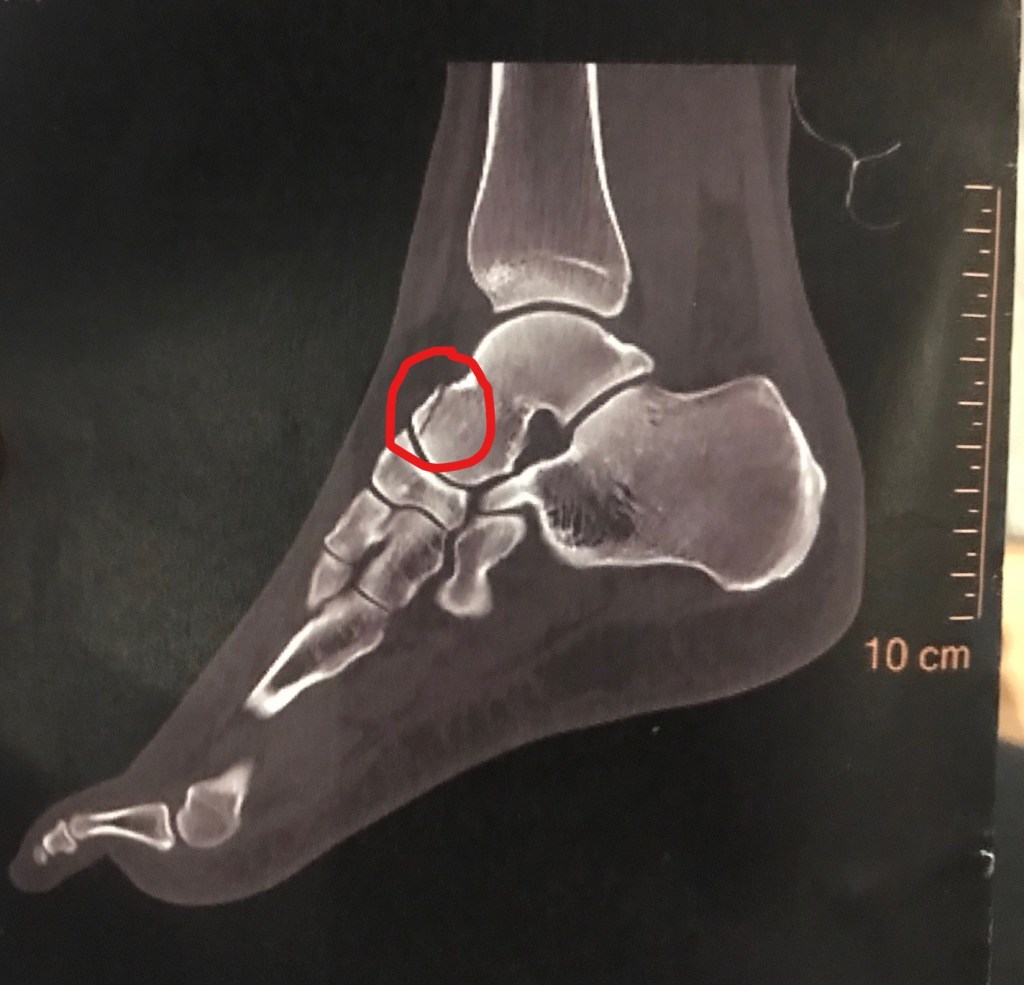

Donc à J+7, scanner. J+8, je reçois les résultats en ligne. Diagnostic: fracture articulaire de la tête de l’astragale. Je parcours le rapport du radiologue et n’y trouve pas de terme horrible du style « déplacé », « luxation ». J+9, retour chez le généraliste qui doit bien reconnaître que le diagnostic des urgentistes n’était pas complètement à la ramasse, même sans scanner, mais qui préfère m’envoyer encore confirmer tout ça chez un spécialiste.